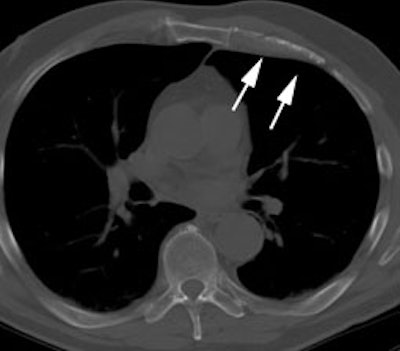

Futile thoracotomy- extensive mediastinal lymph node metastases: The patient below had a T1 lesion in the left lower lobe (black arrow). Pre-operative CT scan revealed lymph nodes within the mediastinum which were not pathologic by size criteria (white arrows). The patient underwent thoracotomy for tumor resection and was found to have positive hilar lymph nodes- a mediastinal node dissection was not performed. A post operative PET scan revealed extensive mediastinal lymph node metastases to the normal sized nodes. Had PET imaging been done pre-operatively, thoracotomy could have been avoided in this patient. |

|